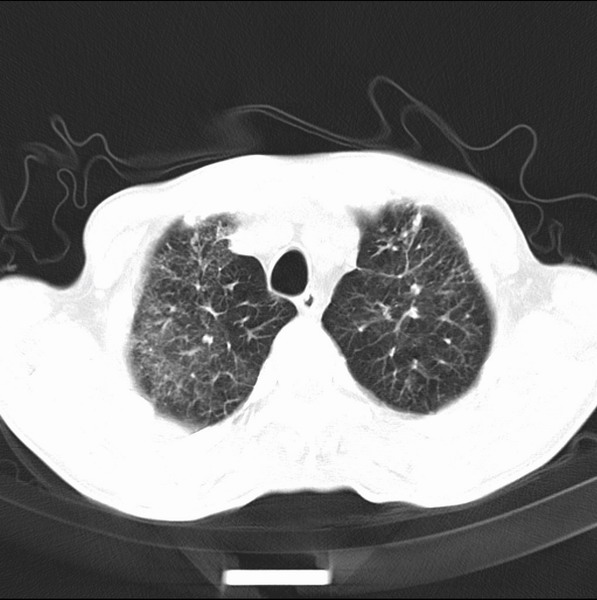

考虑间质性病变,癌性淋巴管炎可能.

转移,癌性淋巴管炎。

建议抗炎后复查,不除外癌性淋巴管炎。

考虑间质性病变,癌性淋巴管炎可能.支持!

支持考虑间质性病变,癌性淋巴管炎可能.